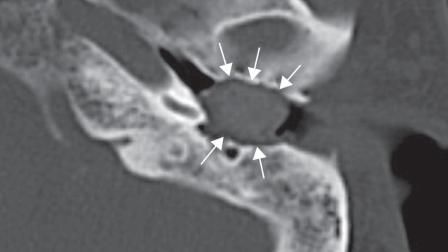

Es importante comenzar con una audiometría, ya que este estudio medimos cómo esta vibrando el tímpano, como se mueven los huesecillos del oído; si el oído interno está bien, e inclusive podemos tener algunos datos que indique cuando el problema pudiera ser neurológico. Frecuentemente el estudio audiológico es suficiente para tener un diagnóstico, otras veces requerimos estudios adicionales.